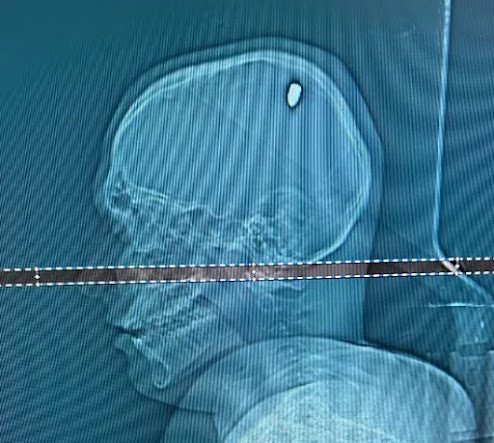

Após exames em um hospital particular de Juiz de Fora, foi identificada a bala, de calibre 9 milímetros, alojada na cabeça dele.

A cirurgia para retirada do projétil durou aproximadamente duas horas. Depois disso, ele permaneceu dois dias na CTI e mais um no quarto, até receber alta. Mateus agora se recupera em casa.